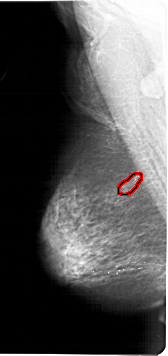

A_1123_1.LEFT_MLO

LEFT_MLO LINES 6751 PIXELS_PER_LINE 3181 BITS_PER_PIXEL 12 RESOLUTION 43.5 OVERLAY

FILE: A_1123_1.LEFT_MLO.OVERLAY

TOTAL_ABNORMALITIES 1

ABNORMALITY 1

LESION_TYPE CALCIFICATION TYPE PLEOMORPHIC DISTRIBUTION SEGMENTAL

LESION_TYPE MASS SHAPE LOBULATED MARGINS ILL_DEFINED

ASSESSMENT 4

SUBTLETY 4

PATHOLOGY BENIGN

TOTAL_OUTLINES 1

BOUNDARY